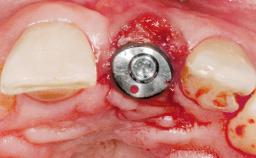

A 42-year-old female patient was referred to our clinic at the School of Dentistry of the University of São Paulo in November 2004, presenting a deficient restoration in the upper left central incisor. The clinical examination revealed no gingival retraction or any signs of gingival inflammation and, therefore, previous periodontal treatment was not considered. The patient presented a high lip line at full smile and a thin tissue biotype. This combination characterized a high-risk situation from an anatomic point of view, which required careful preoperative planning and cautious surgical execution.

Placement Protocol Immediate implant placement

Socket Morphology Single-root socket

Socket Integrity Sufficient, with intact bone walls

Bone Volume Sufficient, with intact walls